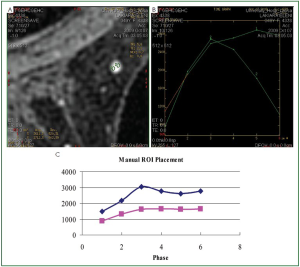

That observation motivated us to conduct a retrospective study of 115 MRMs in order to find the reason for this artifact and to find out ways of avoiding it. For each lesion, the ROI was placed manually in the six images, which correspond to the six phases of the dynamic acquisition, and the signal intensity was measured. Moreover, it was ensured that the ROI was positioned in the same area of the lesion by measuring the distances from the periphery of the ROI to stable points on skin, muscle, ribs and sternum that appear at the image (Figure 2) due to the fact that these points do not significantly change during enhancement in dymanic sequences. It must be stated that these stable points had a specific characteristic, which could be easily identified in all the phases. Furthermore, at least two such stable points were used in positioning the ROI in each phase based on both the distance and angle between the periphery of the ROI and each stable point. In homogeneous lesions, the ROI was positioned in the center of the lesion and subsequently the measurements from the stable points were used to verify the correct of position of the ROI. Skin and muscle have a homogeneous enhancement, whereas the periphery of sternum and ribs have no enhancement whatsoever since they are composed of ossified tissue. Finally, the kinetic curves were manually derived based on the signal intensity-to-time. The manually derived curves were compared to the derived curves by the software of the system regarding their type (Figure 3). The whole procedure was performed by the same radiologist with experience in breast MRI.

Figure 3. (A) Placement of two different ROIs in the same lesion shown in Figure 1, in the third phase of the dynamic sequence, at the periphery of the lesion. (B) The kinetic curves, which have been produced using the software of the system and correspond to the ROIs of image (A). (C) Derivation of the kinetic curves using the manual procedure. We observe that there is an extensive change in the type of the kinetic curves between the two procedures (system software, manual) of kinetic curve derivation. Furthermore, the kinetic curves that are produced using the software of the system show a large variation depending on the position of the ROI used, even though the lesion is fairly homogeneous, whereas the kinetic curves that are produced manually show consistency (type II).